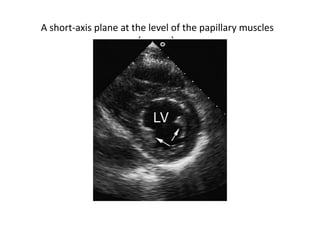

By moving the transducer to a lower interspace and angling the scan

plane more apically, the image will sweep through the papillary

muscle level and then the left ventricular apex .

This series of views is ideal for assessing the contractile pattern of

the left ventricle at the midventricular and apical levels.

A short-axis plane at the level of the papillary muscles

(arrows).

By moving thetransducer to a lower interspace and angling the scan plane more apically, the image will sweep through the papillary muscle level and then the left ventricular apex . This series of views is ideal for assessing the contractile pattern of the left ventricle at the midventricular and apical levels.

A short-axis planeat the level of the papillary muscles (arrows).